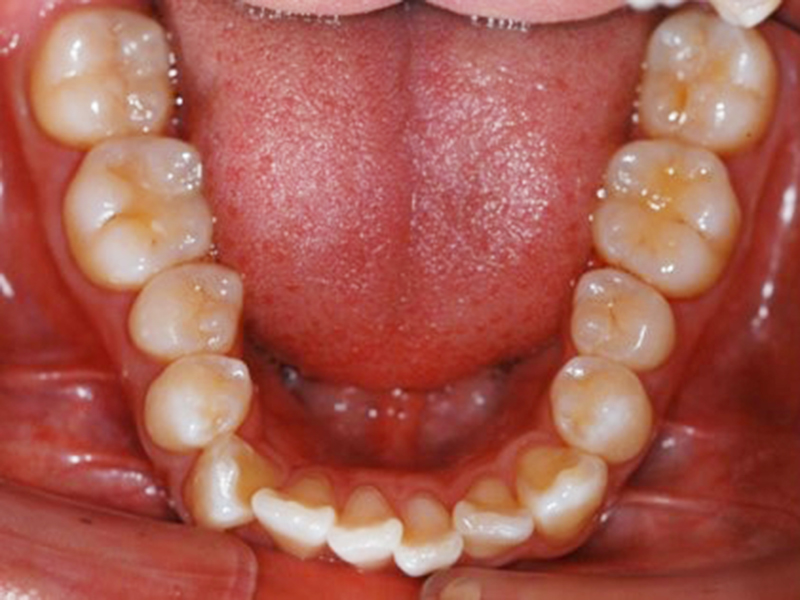

初診時口腔内写真